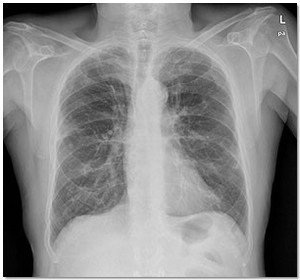

Los investigadores del proyecto se han centrado en dos aspectos básicos del diagnóstico y seguimiento de los pacientes con EPOC. Por un lado, han evaluado la eficacia en el uso de la espirometría, prueba que se realiza de forma rutinaria en los servicios de neumología, en los Centros de Atención Primaria, ya que juegan un papel esencial en el seguimiento de enfermedades respiratorias crónicas como el EPOC o el asma. Para ello se ha diseñado una aplicación que permite desplegar un programa de control de calidad de las mismas. Transcurridos 12 meses de aplicación del programa, los resultados obtenidos demuestran un aumento en la calidad de las mismas, permitiendo un mejor diagnóstico o seguimiento de la EPOC.

El otro objetivo del proyecto ha sido realizar un programa de rehabilitación para pacientes diagnosticados con EPOC. El programa se divide en dos periodos. En el primero el paciente asiste a un entrenamiento en el hospital durante dos meses; y en el segundo se le propone una rutina de ejercicio fuera del hospital para que practique actividades físicas comunes –caminar, ir en bicicleta, etc.-. El control del paciente se realiza desde su domicilio mediante un pulsioxímetro conectado a un teléfono móvil que envía los datos al centra de salud.

El estudio ha demostrado que el hecho de alcanzar niveles adecuados de actividad física diaria, junto con el programa de rehabilitación controlado, es eficaz para mantener e incluso incrementar los efectos del entrenamiento en pacientes con EPOC. Los parámetros medidos en cuanto a calidad de vida y capacidad de esfuerzo mejoran considerablemente en los pacientes que han seguido el programa, como demuestra la medida de la tolerancia al ejercicio, que aumenta de forma notable en el grupo intervenido respecto al control. Con esta tecnología móvil se consigue educar a personas con esta enfermedad, promover un estilo de vida saludable y mejorar el tratamiento –farmacológico y no-farmacológico -, lo hace que los pacientes incrementen su calidad de vida e ingresen con menos frecuencia en el hospital.

Las conclusiones a las que se han llegado con este proyecto indican que el hecho de realizar un diagnóstico precoz y el pautar una rutina de ejercicio controlada y seguida por los especialistas, son componentes clave en el manejo de estos pacientes, aumentando su esperanza de vida y contribuyendo a la contención del gasto sanitario.